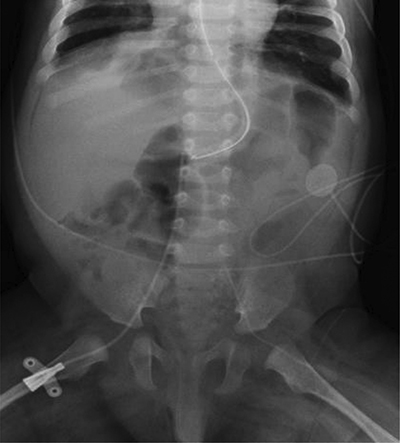

At 14 weeks of corrected age, the patient developed an episode of bronchiolitis. Thoracic radiography showed multiple pulmonary opacities and an air bronchogram suggesting pneumonia (Figure 1), treated with antibiotics, and abdominal radiography showed hyperinflation (Figure 2).

Figure 2

Abdominal radiograph.

Hyperinflation and lateral abdominal subcutaneous emphysema.